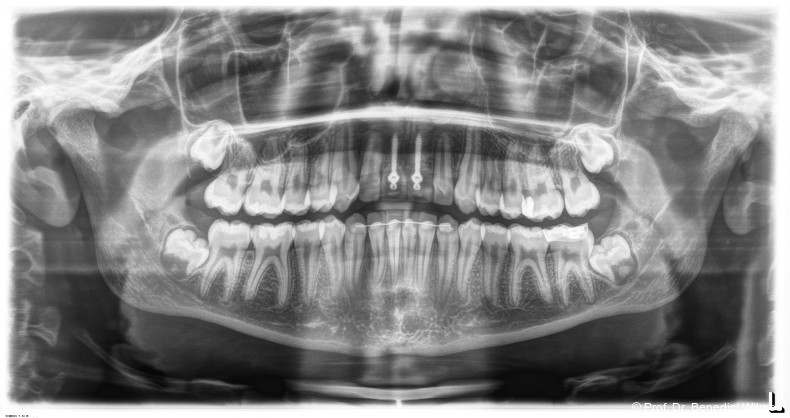

Ein 14-jähriger Patient wurde bei Aplasie der beiden oberen seitlichen Schneidezähne mit dem Ziel der beidseitigen Lückenöffnung kieferorthopädisch therapiert (Abb. 1a+b). Zum Ende der kieferorthopädischen Behandlung wurden zwei Miniimplantate in Regio 2er als temporärer Zahnersatz inseriert (Benefit System, PSM, 2 x 13 mm, Abb. 2a+b). Nach Abdrucknahme wurden Kronen auf den Peek-Abutments modelliert und diese mit Kunststoff auf die Abutments geklebt (Abb. 3a–d). In den Abbildungen 3 und 4 sind die klinischen und röntgenologischen Nachkontrollen innerhalb der nächsten achteinhalb Jahre dokumentiert. Man erkennt einen sowohl in der Höhe als auch in bukkopalatinalen Breite verbleibenden gesunden Knochen ohne Anzeichen einer Atrophie. Im Alter von 23 Jahren wurden die definitiven Implantate ohne die Notwendigkeit einer Augmentation eingesetzt (Abb. 5) und nach Einheilung prothetisch versorgt (Abb. 6a–e und Abb. 7a–c).